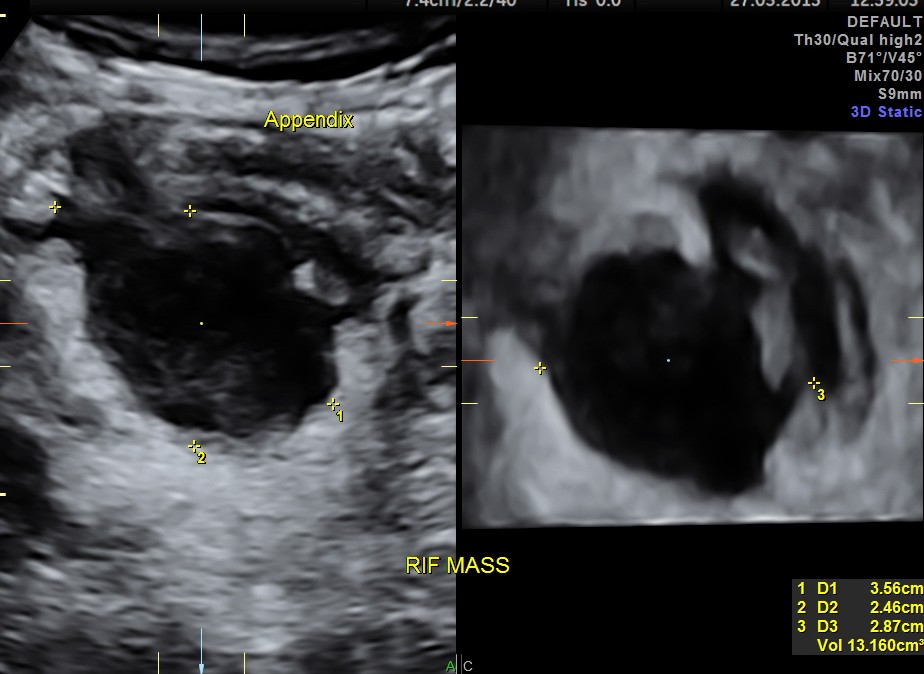

The RIF showed the inflamed appendix communicating with an appendicular mass beneath it.

The following shows the 3 d findings .

The ultrasound diagnosis was acute appendicitis with appendicular mass.